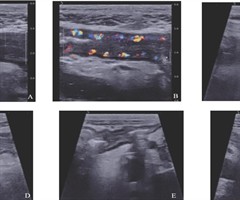

经腹肠道超声与磁共振小肠造影对炎症性肠病狭窄诊断价值的比较

摘要:目的比较经腹肠道超声(IUS)与磁共振小肠造影(MRE)对炎症性肠病(IBD)肠道狭窄的诊断价值。方法回顾性分析2021年1月至2025年2月就诊于首都医科大学附属北京友谊医院同期行IUS与MRE的51例IBD 患者的影像学特征,以内...